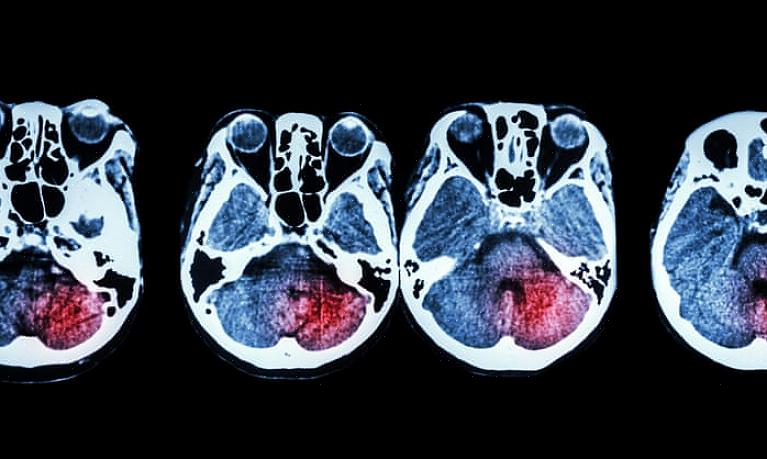

המוח והגרלה

לפני שאתם מחליטים שזכייה בלוטו היא הדרך היחידה לחיות חיים מאושרים ונטולי דאגות, קחו רגע לחשוב איך המוח מגיב לדברים בנאליים. למשל, האם אתה לא לובש את אותו הדבר כל הזמן, למרות שיש לך ארון מלא בבגדים? למה אתה תמיד רוצה מכונית טובה יותר מזו שיש לך? בית גדול יותר? בכל כך הרבה היבטים של חייך, האם מה שיש לך באמת לא מספיק?

תגובות ותחושות אלו מגיעות ממרכזי התגמול של המוח. הגירוי, ההגרלה, הופך למשהו רצוי כשאנו מוסיפים אותו להתנהגות ואמונות נלמדות. עם זאת, ברגע שאתה מקבל את מה שאתה רוצה, מה המוח צריך להרגיש כך שוב? זה צריך לזכות בלוטו או לקבל יותר כסף.